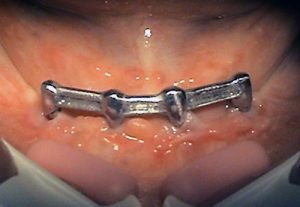

Prosthetic treatment in a toothless jawbone carried - 5 implants

1. PHASE - implant placement

2. PHASE - state before the provisional solution was made

3. PHASE - making a temporary solution

4.PHASE - implant placement